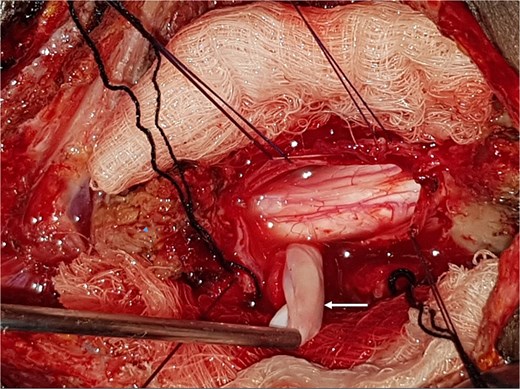

A 12-year-old girl presented to us with progressive weakness of the lower limbs of 11 months duration. There was associated paraesthesia and spasms but no sphincteric dysfunction. Clinical examination revealed an otherwise healthy young girl with normal mental status. She had spastic paraparesis (power Grades 3 to 4) and exaggerated muscle stretch reflexes in the lower limbs. The sensory level was T4. There was no gibbus or spinal tenderness. Other systemic examination findings were normal. A clinical diagnosis of T4 non-traumatic myelopathy, Frankel D was made. Thoracic spine MRI showed an extradural lesion with similar intensities to CSF on all sequences posterior to the spinal cord at T4–T8 as well as significant cord compression at the same levels (Fig. 3) [12]. A diagnosis of thoracic spine EAC was made. We approached the lesion through T4–T8 laminectomies. Intra-operative finding was that of a large extradural cyst which communicated with the subarachnoid space through a dorsolaterally located pedicle near the nerve sleeve at T7. The cyst was excised completely and the dura defect closed without duroplasty (Fig. 4) [12]. The post-operative course was uneventful and she was discharged on the 24th post-operative day. She was last seen 48 months post-surgery. At the time, she was ambulating without support with power of Grade 5 in the lower limbs.

Sagittal T1-weighted (a) and T2-weighted (b) thoracic spine MRI showing an extradural cyst at T4–T8 compressing the cord anteriorly [12].